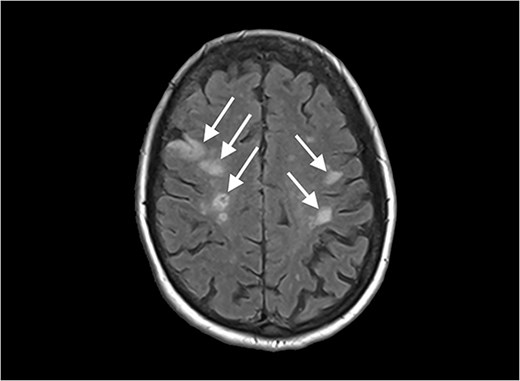

Echocardiography revealed a 1.2 cm pedunculated mass attached to the anterior mitral valve leaflet (AMVL) with severe mitral regurgitation (Fig. 1). Computed tomography imaging revealed multiple hepatic lesions (suspected septic emboli, Fig. 2), and a cavitating mass in the posterior aspect of the left upper lobe of the lung (Figs 3 and 4). Magnetic resonance imaging showed multiple cerebral lesions (Fig. 5), also thought to be septic emboli. Her presentation was suspected to be due to infective endocarditis rather than ischaemic, as troponin was negative, and coronary angiography was unremarkable. She was therefore treated promptly with intravenous vancomycin and gentamicin as per local antimicrobial guidelines. However, she failed to recover, and her case was reviewed in the regional in-house urgent cardiac surgical multidisciplinary team meeting. Considering her persistent fever, as well as the recurrent emboli, the decision was made to transfer her to our centre for emergency surgery.

Diffusion-weighted magnetic resonance imaging image of the brain, showing multiple lesions.